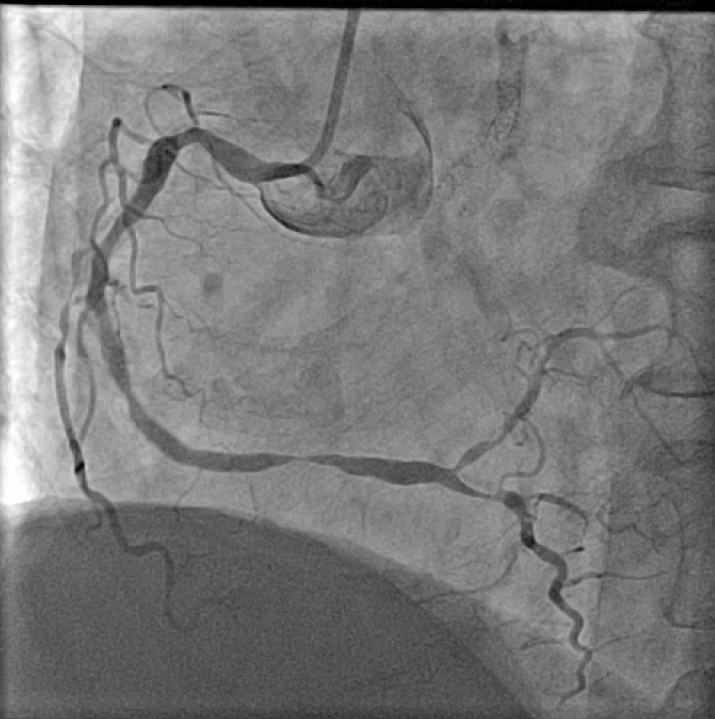

Distal LM intermediate disease, significant proximal LAD ISR, significant mid LCx stenosis. Diffuse high-grade RCA disease (proximal to distal into RPDA). Calcific and angulated proximal RPDA.

In view of severe left ventricular dysfunction, a 40cc IABP was inserted via the right common femoral artery for mechanical circulatory support during PCI. A 6Fr AL1 guide catheter was advanced via the right radial artery to selectively cannulate the right coronary artery (RCA). A Runthrough NS coronary guidewire was advanced into the distal R-PDA. Balloon angioplasty was performed from RPDA back to proximal RCA using a 2.5x15mm Sapphire3 NC balloon to 12atm. A Boston Scientific Opticross HD 60MHz IVUS catheter was advanced into the distal RPDA and intravascular imaging performed. Unfortunately, upon completion of the pullback run, the IVUS catheter could not be withdrawn. The IVUS catheter was stuck on the calcific and angulated segment in the proximal RPDA. Despite use of focused force technique, parallel ballooning, the IVUS catheter could not be withdrawn. During the attempts, the IVUS catheter inadvertently broke, leaving a short segment of the catheter in the RPDA. Check angiography showed no flow impairment. Thus, proximal to mid RCA was stented using a 3.0x38mm DES and a 3.5x48mm DES. Due to long procedural time, decision made to stage further PCI to the next day. The following day, PCI to LAD was performed uneventfully. The RCA was cannulated using a 7Fr AL2 guide catheter via right radial artery. A Sion Blue ES guidewire was advanced into the RPDA. A 6Fr Liquid guide extension catheter was advanced across the stented segments. A 3.2Fr EnSnare used to withdraw IVUS.